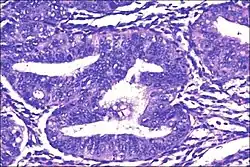

Micrograph showing simple endometrial hyperplasia, where the gland-to-stroma ratio is preserved but the glands have an irregular shape and/or are dilated. Endometrial biopsy. H&E stain.

Like other hyperplastic disorders, endometrial hyperplasia initially represents a physiological response of endometrial tissue to the growth-promoting actions of estrogen. However, the gland-forming cells of a hyperplastic endometrium may also undergo changes over time which predispose them to cancerous transformation. Several histopathology subtypes of endometrial hyperplasia are recognisable to the pathologist, with different therapeutic and prognostic implications.[4]